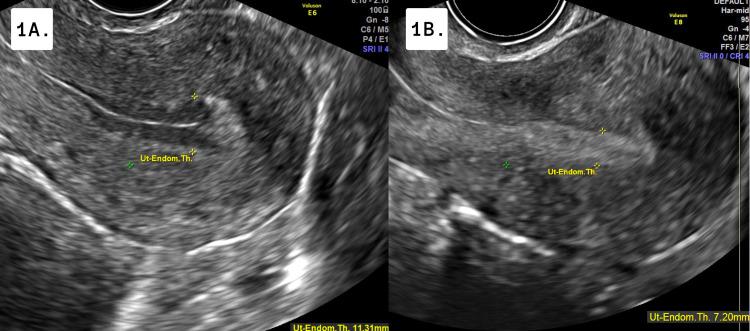

Curcumin is a commonly used herbal supplement purported for its antioxidant, anti-inflammatory, and antineoplastic properties. The effects of curcumin supplementation on endometrial lining have been proposed; however, endometrial preparation in the case of frozen-thawed embryo transfer (FET) has not been established. This case series references two scenarios where turmeric was ingested by the patient, and endometrial thickness was subsequently reduced disrupting the FET cycle. Throughout this case series, curcumin's possible interactions with the uterine lining are summarized. Additionally, these cases highlight the importance of physicians' awareness of taking a full history of any herbal remedies or supplements in addition to prescription or over-the-counter medications taken when undergoing treatment for controlled FET cycles or in-vitro fertilization (IVF). To our knowledge, no studies to date have investigated this relationship.

姜黄素是一种常用的草药补充剂,据称具有抗氧化、抗炎和抗肿瘤特性。有人提出了补充姜黄素对子宫内膜的影响;然而,在冻融胚胎移植(FET)情况下的子宫内膜准备方法尚未确定。本病例系列参考了两个患者摄入姜黄的案例,随后子宫内膜厚度降低,扰乱了FET周期。在整个病例系列中,总结了姜黄素与子宫内膜可能的相互作用。此外,这些案例强调了医生了解患者完整用药史的重要性,除了正在接受控制性FET周期治疗或体外受精(IVF)时所服用的处方药或非处方药外,还应包括任何草药疗法或补充剂。据我们所知,迄今为止尚无研究调查这种关系。